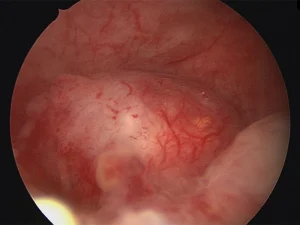

عوارض کولپوسکوپی معمولا خفیف و گذرا هستند، اما آگاهی از آنها برای هر زنی که قصد انجام این بررسی تشخیصی را دارد ضروری است. کولپوسکوپی

تفسیر جواب کولپوسکوپی؛ راهنمای کامل خواندن و تفسیر نتایج

تفسیر جواب کولپوسکوپی یکی از دغدغههای رایج بانوان پس از انجام این آزمایش است. بسیاری از افراد پس از دریافت نتیجه نمیدانند معنی اصطلاحات و

آمادگی های قبل از کولپوسکوپی رحم که باید درباره آن ها بدانید

آشنایی و رعایت آمادگیهای قبل از کولپوسکوپی رحم، نه تنها احتمال بروز خطا در تشخیص را کاهش میدهد، بلکه تجربه بیمار را نیز خوشایندتر و

مراقبت های بعد از کولپوسکوپی رحم؛ راهنمای جامع بیماران

مراقبتهای بعد از کولپوسکوپی رحم نقش مهمی در روند بهبود و پیشگیری از عوارض احتمالی دارند. کولپوسکوپی روشی تخصصی برای بررسی دهانه رحم است که